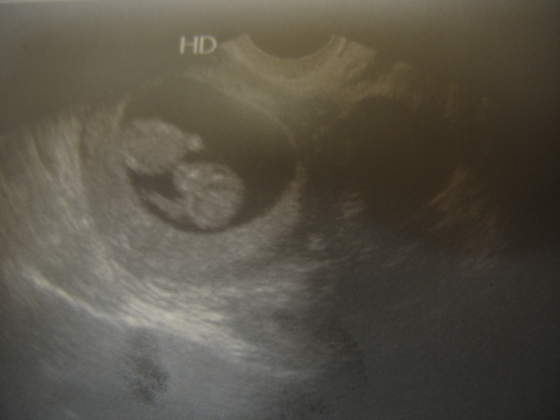

Dziewczynki, byłam dzisiaj u lekarza i dostałam skierowanie na USG. Umóiłam się na jutro, więc wieczorkiem pewnie coś wkleję :-) Nie mogę się doczekać. To będzie zwykłe usg, poznam wymiary i może coś więcej nt rzeczywistego tygodnia ciąży. Potem do 14 tyg zrobię genetyczne, w tym 3D i już nie mogę się doczekać.